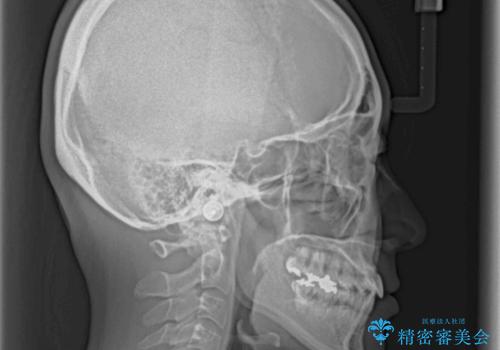

- 下顎の歯が舌側に倒れていることと、前歯の咬み合わせの不具合を気にして来院された患者様です。

受け口傾向の口元であるため、下顎左右小臼歯各1歯を抜歯して歯列を整えることとしました。

前歯には治療中の仮歯が装着されていたため、矯正治療後にオールセラミッククラウンにて補綴治療を行うこととしました。